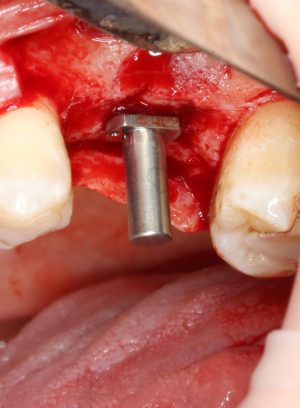

После этого можно поставить пин и проверить направление и ангуляцию оси будущего имплантата.

Кстати, о пинах. В Astra Tech они, сцуко, хитрые. Диаметр тонкого конца 2.0 мм, а толстого — 3.2 мм. Это значит, что измерить и оценить ось имплантата мы можем на этапе пилотной фрезы (2.0 мм) и следующей за ней «зеленой» (3.2 мм). Далее точные изменения становятся невозможными. Платформа-ограничитель имеет размеры 3.5 (по узкой) и 5.0 (по широкой частям) мм, что позволяет оценить положение будущей лунки относительно других имплантов и соседних зубов в окклюзионной плоскости.